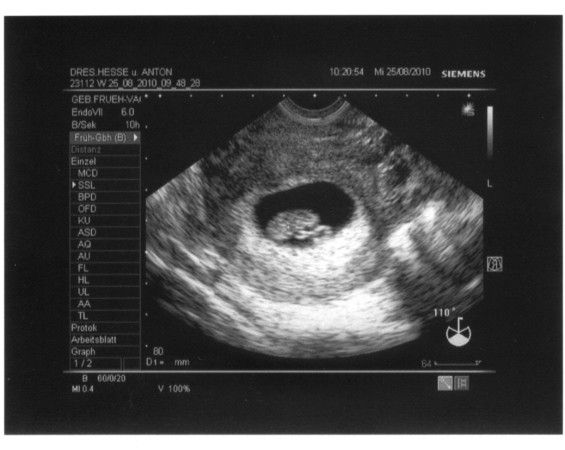

1.US_samulu_ET01042010

25.08.2010

zusehen ist schön der Embryo SSL 18mm; Markierung + ist Herzchen; rechts unten Nabelschnur und noch Dottersack

daraus ergibt sich eine Summe von ALLES OK in der 9.SSW (SSW8+5T)